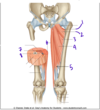

Which muscle is labeled by #4?

Piriformis

Which structure is indicated by #2?

What is its primary function?

Piriformis

Lateral rotation of the hip